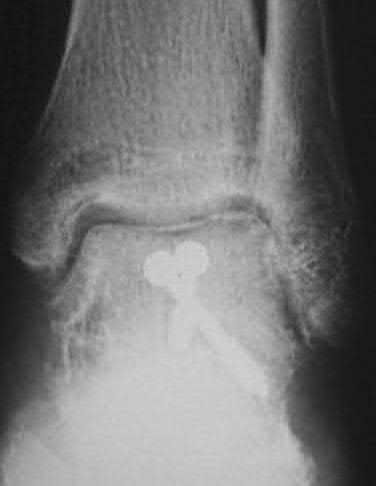

A 25-year-old male sustains an ankle fracture dislocation and undergoes open reduction and internal fixation. He returns to clinic five months following surgery complaining of continued ankle pain and instability with weight bearing. His immediate post-operative AP radiograph is seen in Figure A. Which of the following could have prevented this patient from developing persistent pain?

The patient presents with continued ankle pain and instability following open reduction and internal fixation. The radiograph in figure A demonstrates inadequate restoration of fibular length, likely leading to continued tibiotalar instability.